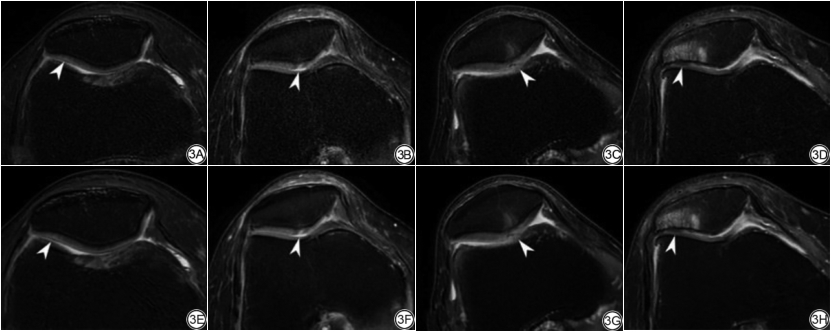

两名医师分别基于膝关节2D FSEO及FSEDL图像对膝关节结构异常进行评估,κ值在0.954~1.000之间,P<0.05。同一名医师对FSEO图像和FSEDL图像的诊断结果比较,关于软骨缺损的检测和评估,诊断结果具有较好的一致性,κ值分别为0.769、0.771,P<0.05(表5、图3);关于半月板、韧带、骨髓及滑膜液的检测和评估,诊断结果具有极好的一致性,κ值在0.944~1.000之间,P<0.05(表5、图2~3)。

在诊断效能方面,本研究表明DLR图像和原始图像对膝关节病变的显示基本一致。RECHT等[20]使用了回顾性的欠采样数据显示DL图像可与标准临床图像互换用于检测膝关节内部结构异常,DL加速图像比标准图像具有更高的图像质量。本研究对膝关节结构异常的检出和评估,DLR图像和原始图像总体无明显差异。在软骨缺损分级上,两组图像的一致性的κ值稍低(0.769和0.771),这可能因为图像通过DLR,软骨与邻近结构的对比提高,从而软骨边缘和纹理显示更清晰,因此病变显示更明显。